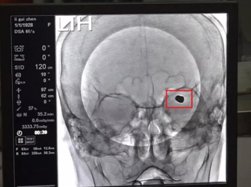

患者术前脑动脉瘤血管造影

李宏宇介绍,李女士脑动脉瘤大小 8mmX6mm,在他多年临床工作中也属罕见。在术前准备后中午 12 时 30 分手术正式开始,通俗讲动脉瘤介入栓塞治疗就是将介入导丝填充进血管瘤内,让血液不再经过血管瘤,从而让这个大脑内部的"*弹炸**"不会因血压"引爆"。

术后填充的动脉瘤

"患者脑部动脉瘤瘤体过大,达到 8mmX6mm,我们说 5mm 是动脉瘤最大观察范围,它已经超过最大观察范围,随时可能会爆裂,导致患者脑内大量出血死亡。手术难度主要是此动脉瘤形态和大脑中动脉的一支血管关系十分密切,我们用一个支架导管保护一条主杆血管,必须在完美填塞大动脉瘤的前提下,保护好周边两根重要血管。"李宏宇说。